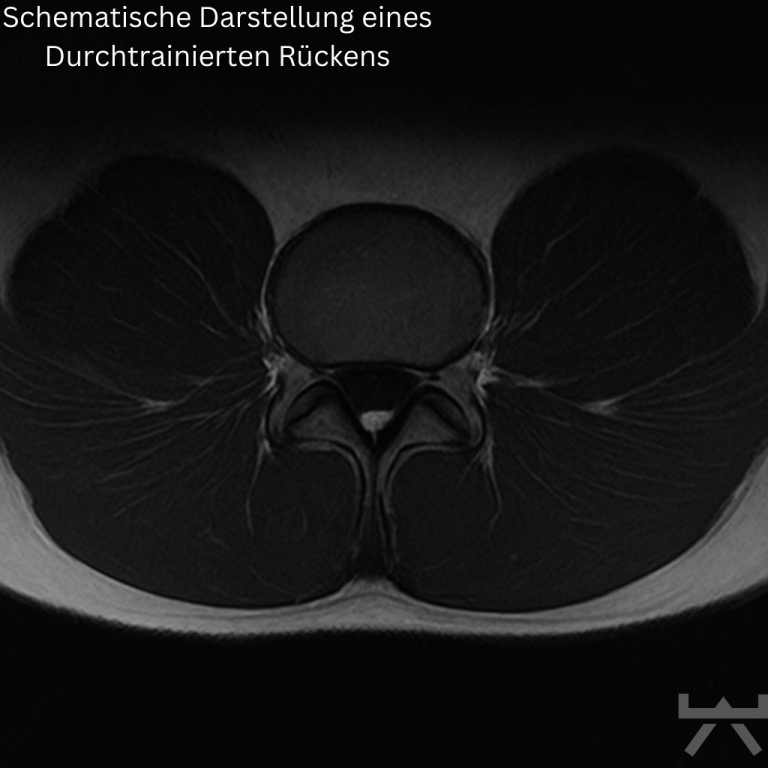

Über die Jahre geht nicht nur Muskelmasse und dementsprechend auch Muskelkraft verloren, sondern auch die Muskellänge. Muskelverlust entsteht – genauso wie der Aufbau von Muskulatur – indem die kleinsten Einheiten der Muskelzellen (= die Sarkomere) aufeinander oder nebeneinander ab- bzw. aufgebaut werden. Genau dann, wenn diese Einheiten nebeneinander abgebaut werden, hat der Muskelverlust einen direkten Einfluss auf die Muskellänge. Hinzu kommt, dass die meisten von uns den Alltag hauptsächlich im Sitzen verbringen. Da wir wissen, dass unsere Muskulatur ein dynamisches Gewebe ist, das sich je nach Funktion und Arbeitslänge verkürzen oder verlängern kann, wird ein sitzender Alltag diesen Prozess der Verkürzung höchstwahrscheinlich nicht gerade positiv beeinflussen.